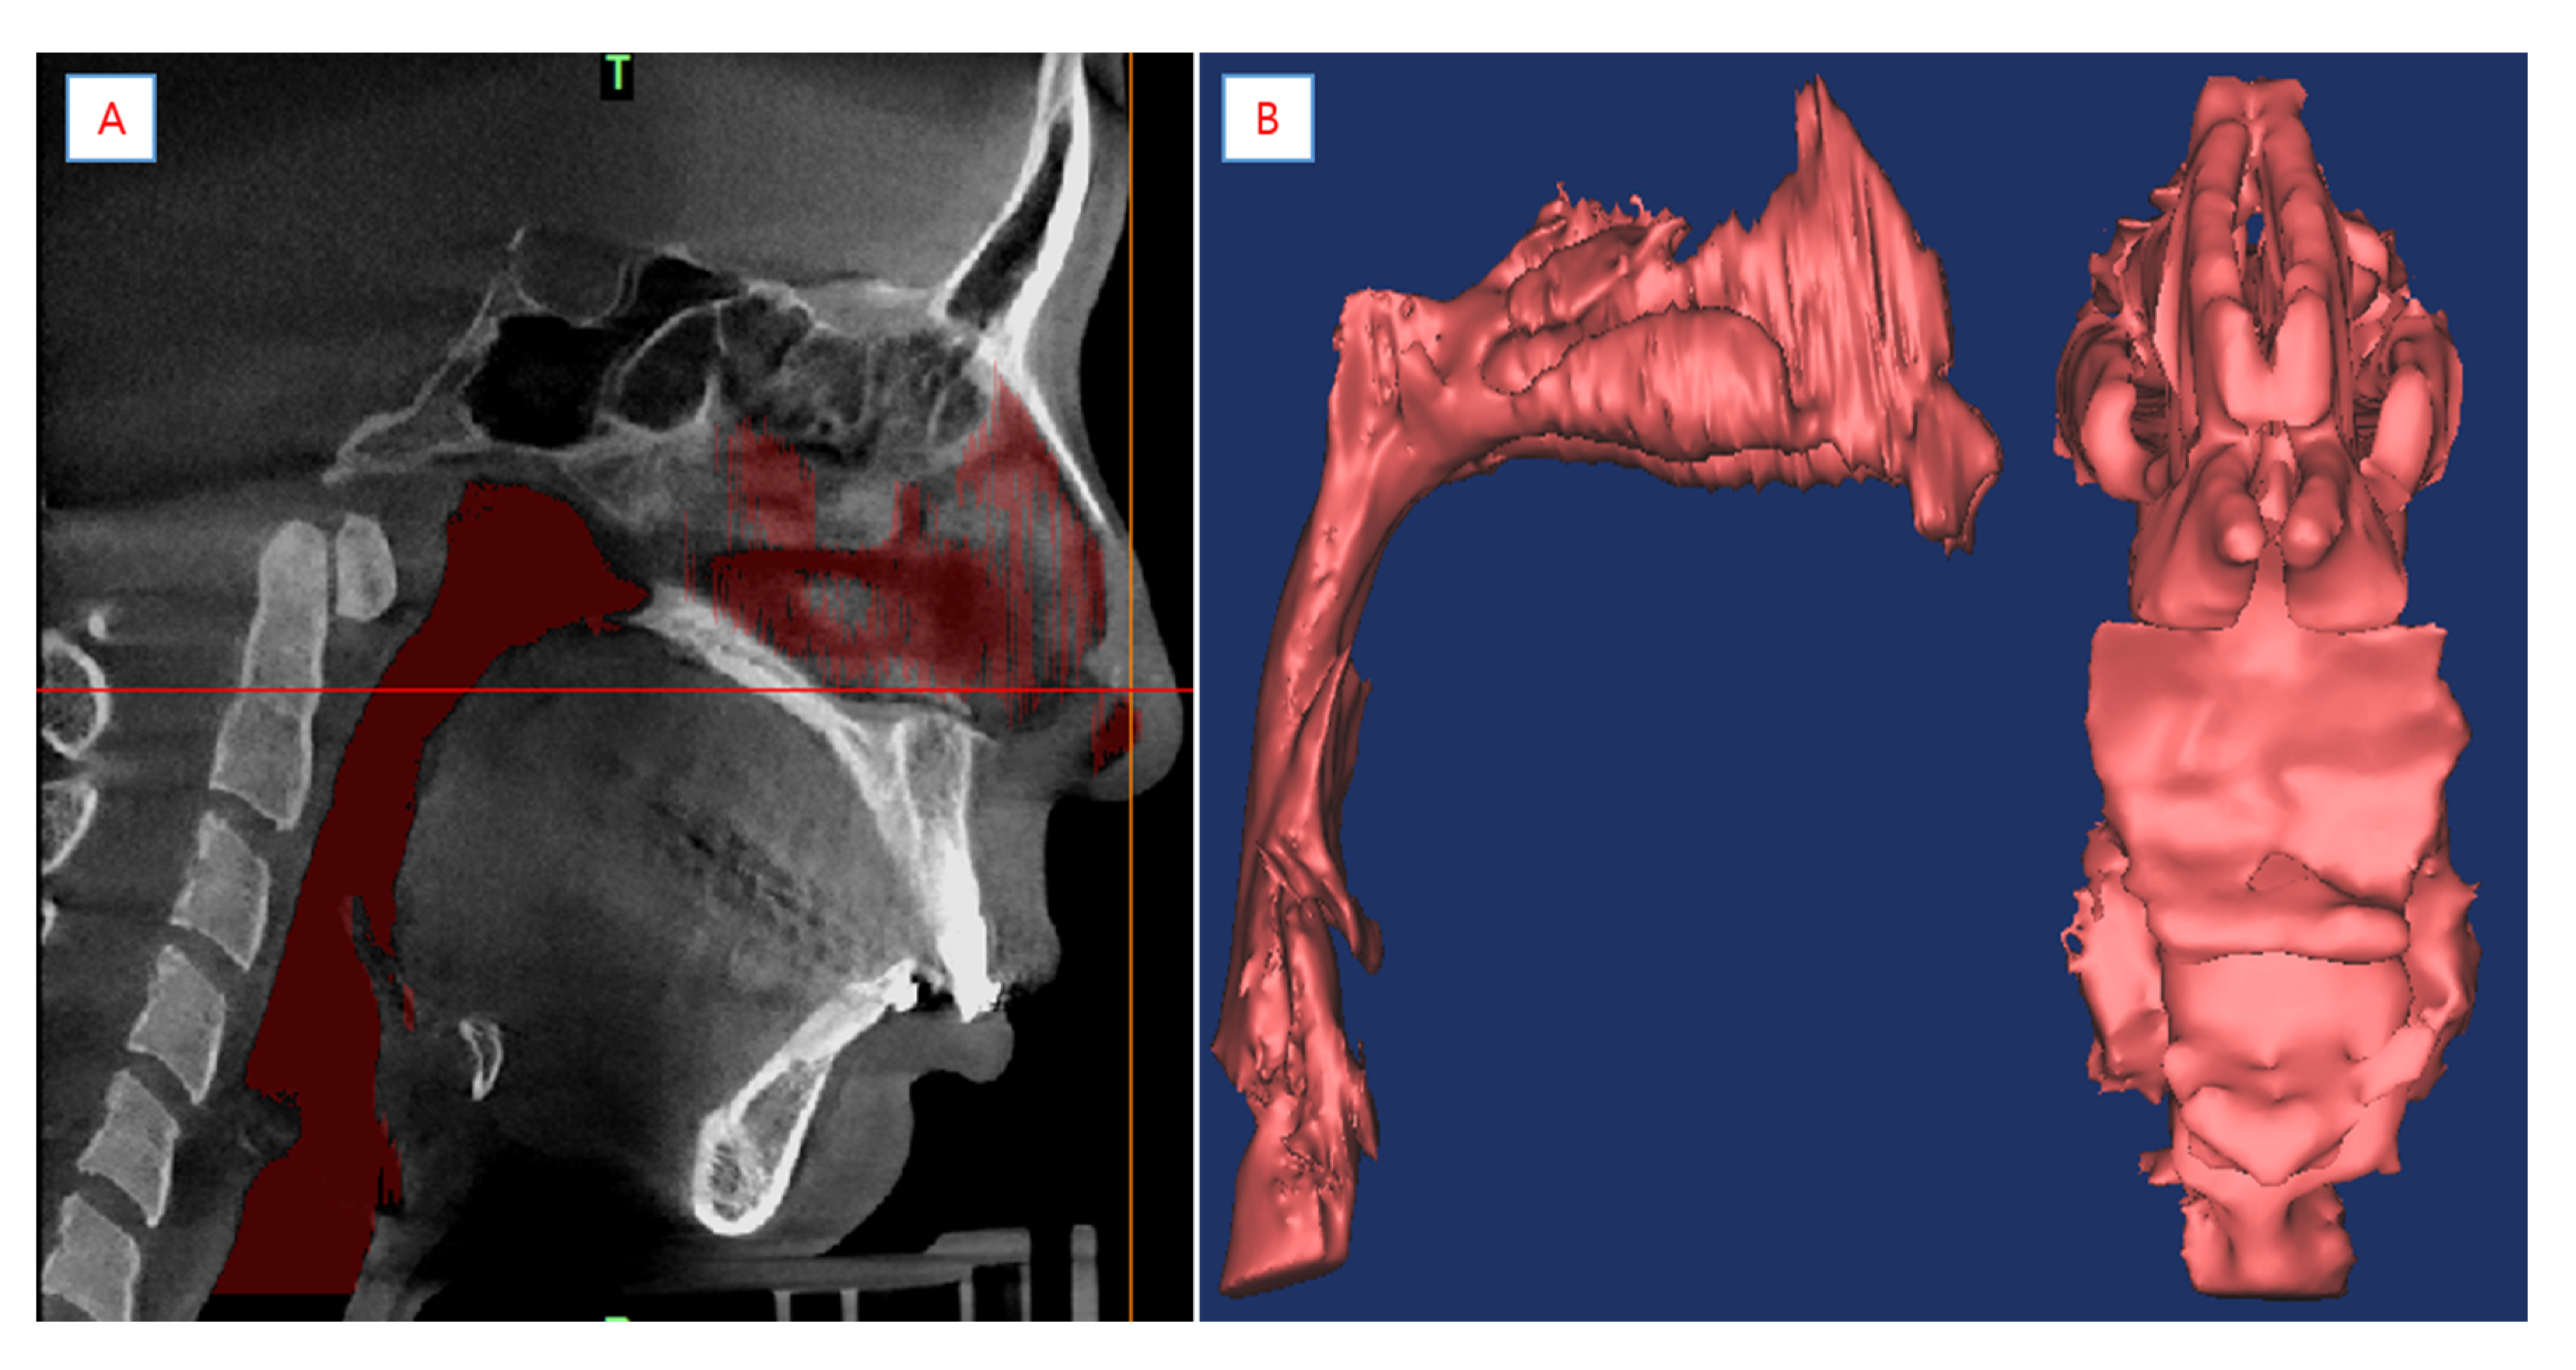

2.3. Reconstruction of the Model and Mesh Generation

The 3D-DOCTOR software was used for the reconstruction of the airway models for all patients. About 600 images of the upper airway were segmented with a threshold value between −1024 to −480 Hounsfield units. Figure 5 shows the anatomy of the upper airway, which has the smallest area. Given the complexity of the morphological characteristics of the upper airway, setting the fluid domain is vital for analysis. As anatomy can significantly change the facial features of people, an understanding of the interior anatomy of humans can solve this problem. The highest number of obstruction sites detected by studies were at the level of the oropharynx [21]. A collapse occurs close to the velopharynx or oropharynx. The total fluid domain was set from the nasal vestibule to the laryngopharynx. Using the CT data, the modeling process was subsequently executed using the following steps. First, the extracted boundary was set on the CT images. Then, the boundary piles on the CT images were laminated, and finally, the model created through the lamination was cleaned and saved in stereolithography (STL) format. It should be noted that numerous other methods can be used for creating models in commercial programs. Anatomically accurate 3D models were converted to the STL format (Figure 5 and Figure 6). The STL files were then imported to the integrated computer engineering and manufacturing code for CFD (ICEM-CFD). Meshing was performed on the prism and tetrahedral meshes generated by ICEM-CFD. The meshing elements and nodes were taken from pre-operation cases at 1.21 × 106 and 6.25 × 106, and post-operation cases at 1.90 × 106 and 6.89 × 106, respectively. The finite volume approaches of the cells’ near-wall boundary were irregular, which may require tailored treatment. The prisms can first create a layer of regular prisms near the wall and then mesh the remaining volume with tetrahedrons. This grid approach gives better solutions and convergence of computation [22]. A grid invariant study was performed to check the grid independence of the simulation meshes. This compared three different meshes (fine: 1.67 × 107 meshes; mild: 8.16 × 106 meshes; and coarse: 4.6 × 106 meshes) for the pre-operative patient 5 model. In terms of average velocity at the minimal cross-sectional area, the coarse case and mild case had a disparity of 2.65% and the disparity within the mild case and fine case was 2.27%. Thus, the meshes in the moderate case proved to be satisfactory for describing the airflow dynamics of the upper airway.

Figure 5. (A) Segmented pharyngeal airway. (B) Anatomical 3D model of pharyngeal airway was created using CBCT.